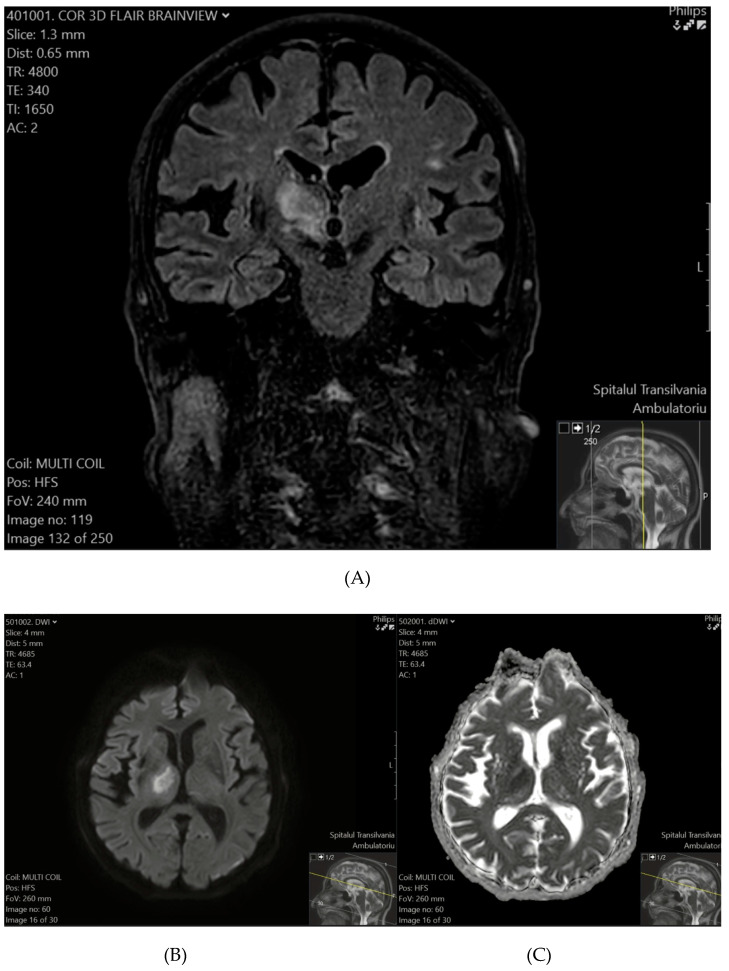

Background: The updated definition of a TIA emphasizes tissue characteristics rather than symptom duration, defining a TIA as a transient neurological episode without ischemic lesions in brain imaging, including in DWI. If imaging reveals a lesion, even in patients with transient symptoms, the event is reclassified as a minor ischemic stroke.

Conclusions: Among the 26 patients clinically diagnosed with TIAs, 7 (26.9%) exhibited ischemic lesions in DWI, reclassifying these cases as minor ischemic strokes under the updated definition. The prevalence of ischemic lesions was notably higher in patients with comorbidities such as hypertension and diabetes. These findings highlight the importance of early MRI-DWI to accurately distinguish TIAs from minor ischemic strokes. Routine urgent DWI within the first week of TIA symptoms enhances diagnosis and risk stratification and can guide targeted stroke prevention strategies, particularly when combined with the ABCD2 score.